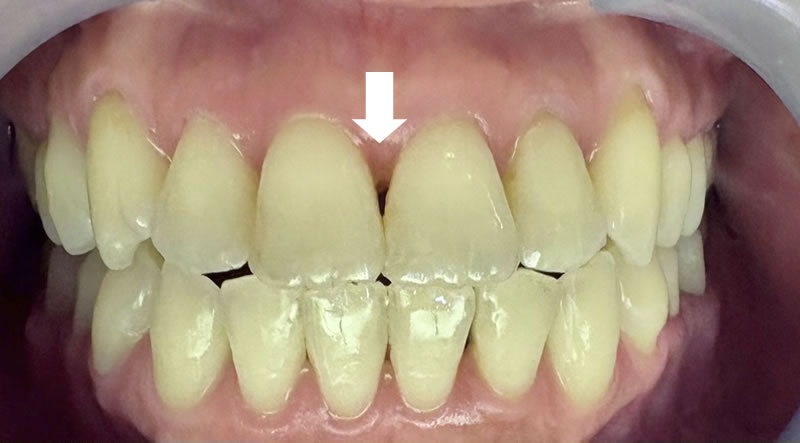

矯正後の60代後半女性で、下の前歯の歯茎下がりの空隙部位に食べものが入ってしまったり唾液が飛ぶから、封鎖したいという主訴でした。

ダイレクトボンディングによる歯の形態修正で足場を作り、ヒアルロン酸をキャリアにした幹細胞由来サイトカインとレーザーによる治癒促進治療による歯周組織再生誘導を同時に併用しました。